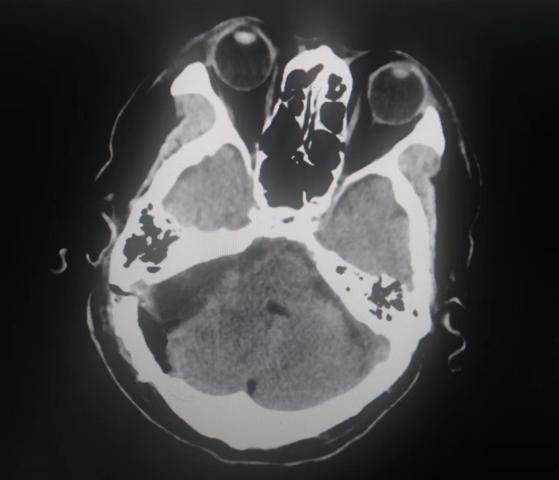

患者入院后,头颅MR检查后发现,小脑右侧长了巨大肿瘤,直径约6公分,患者家属收到不小的惊吓。患者4年前曾做过一次头颅核磁共振,当时肿瘤较小,考虑到患者已经88岁,家人还是决定保守观察,没想到如今,它已经长大到足足有一个土豆那么大,而且患者头晕较重,反复恶心、呕吐,卧床不起,因此必须进行手术,才能解决患者病症。

患者家属反复考虑、综合思量后,决定接受手术治疗。神经外科二病区主任白西民及团队进行综合评估,术前讨论,研究患者肿瘤位置、毗邻关系及心肺状况,制定周密手术方案。联合呼吸科、心内科、麻醉科及重症医学科等学科会诊,研究制定详细手术方案及应急预案。

手术时,在显微镜下沉着应对,先切断肿瘤血液供应控制出血,一边分块切除肿瘤,一边对肿瘤进行精细剥离,仔细保护与肿瘤粘连紧密的重要神经、血管结构,最后在显微镜下全部切除肿瘤,而且完整保留了神经功能,手术取得圆满成功。